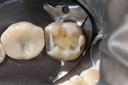

Wayne Chin #2 pre-op

Wayne Chin #2 prep

Wayne Chin #2 finish